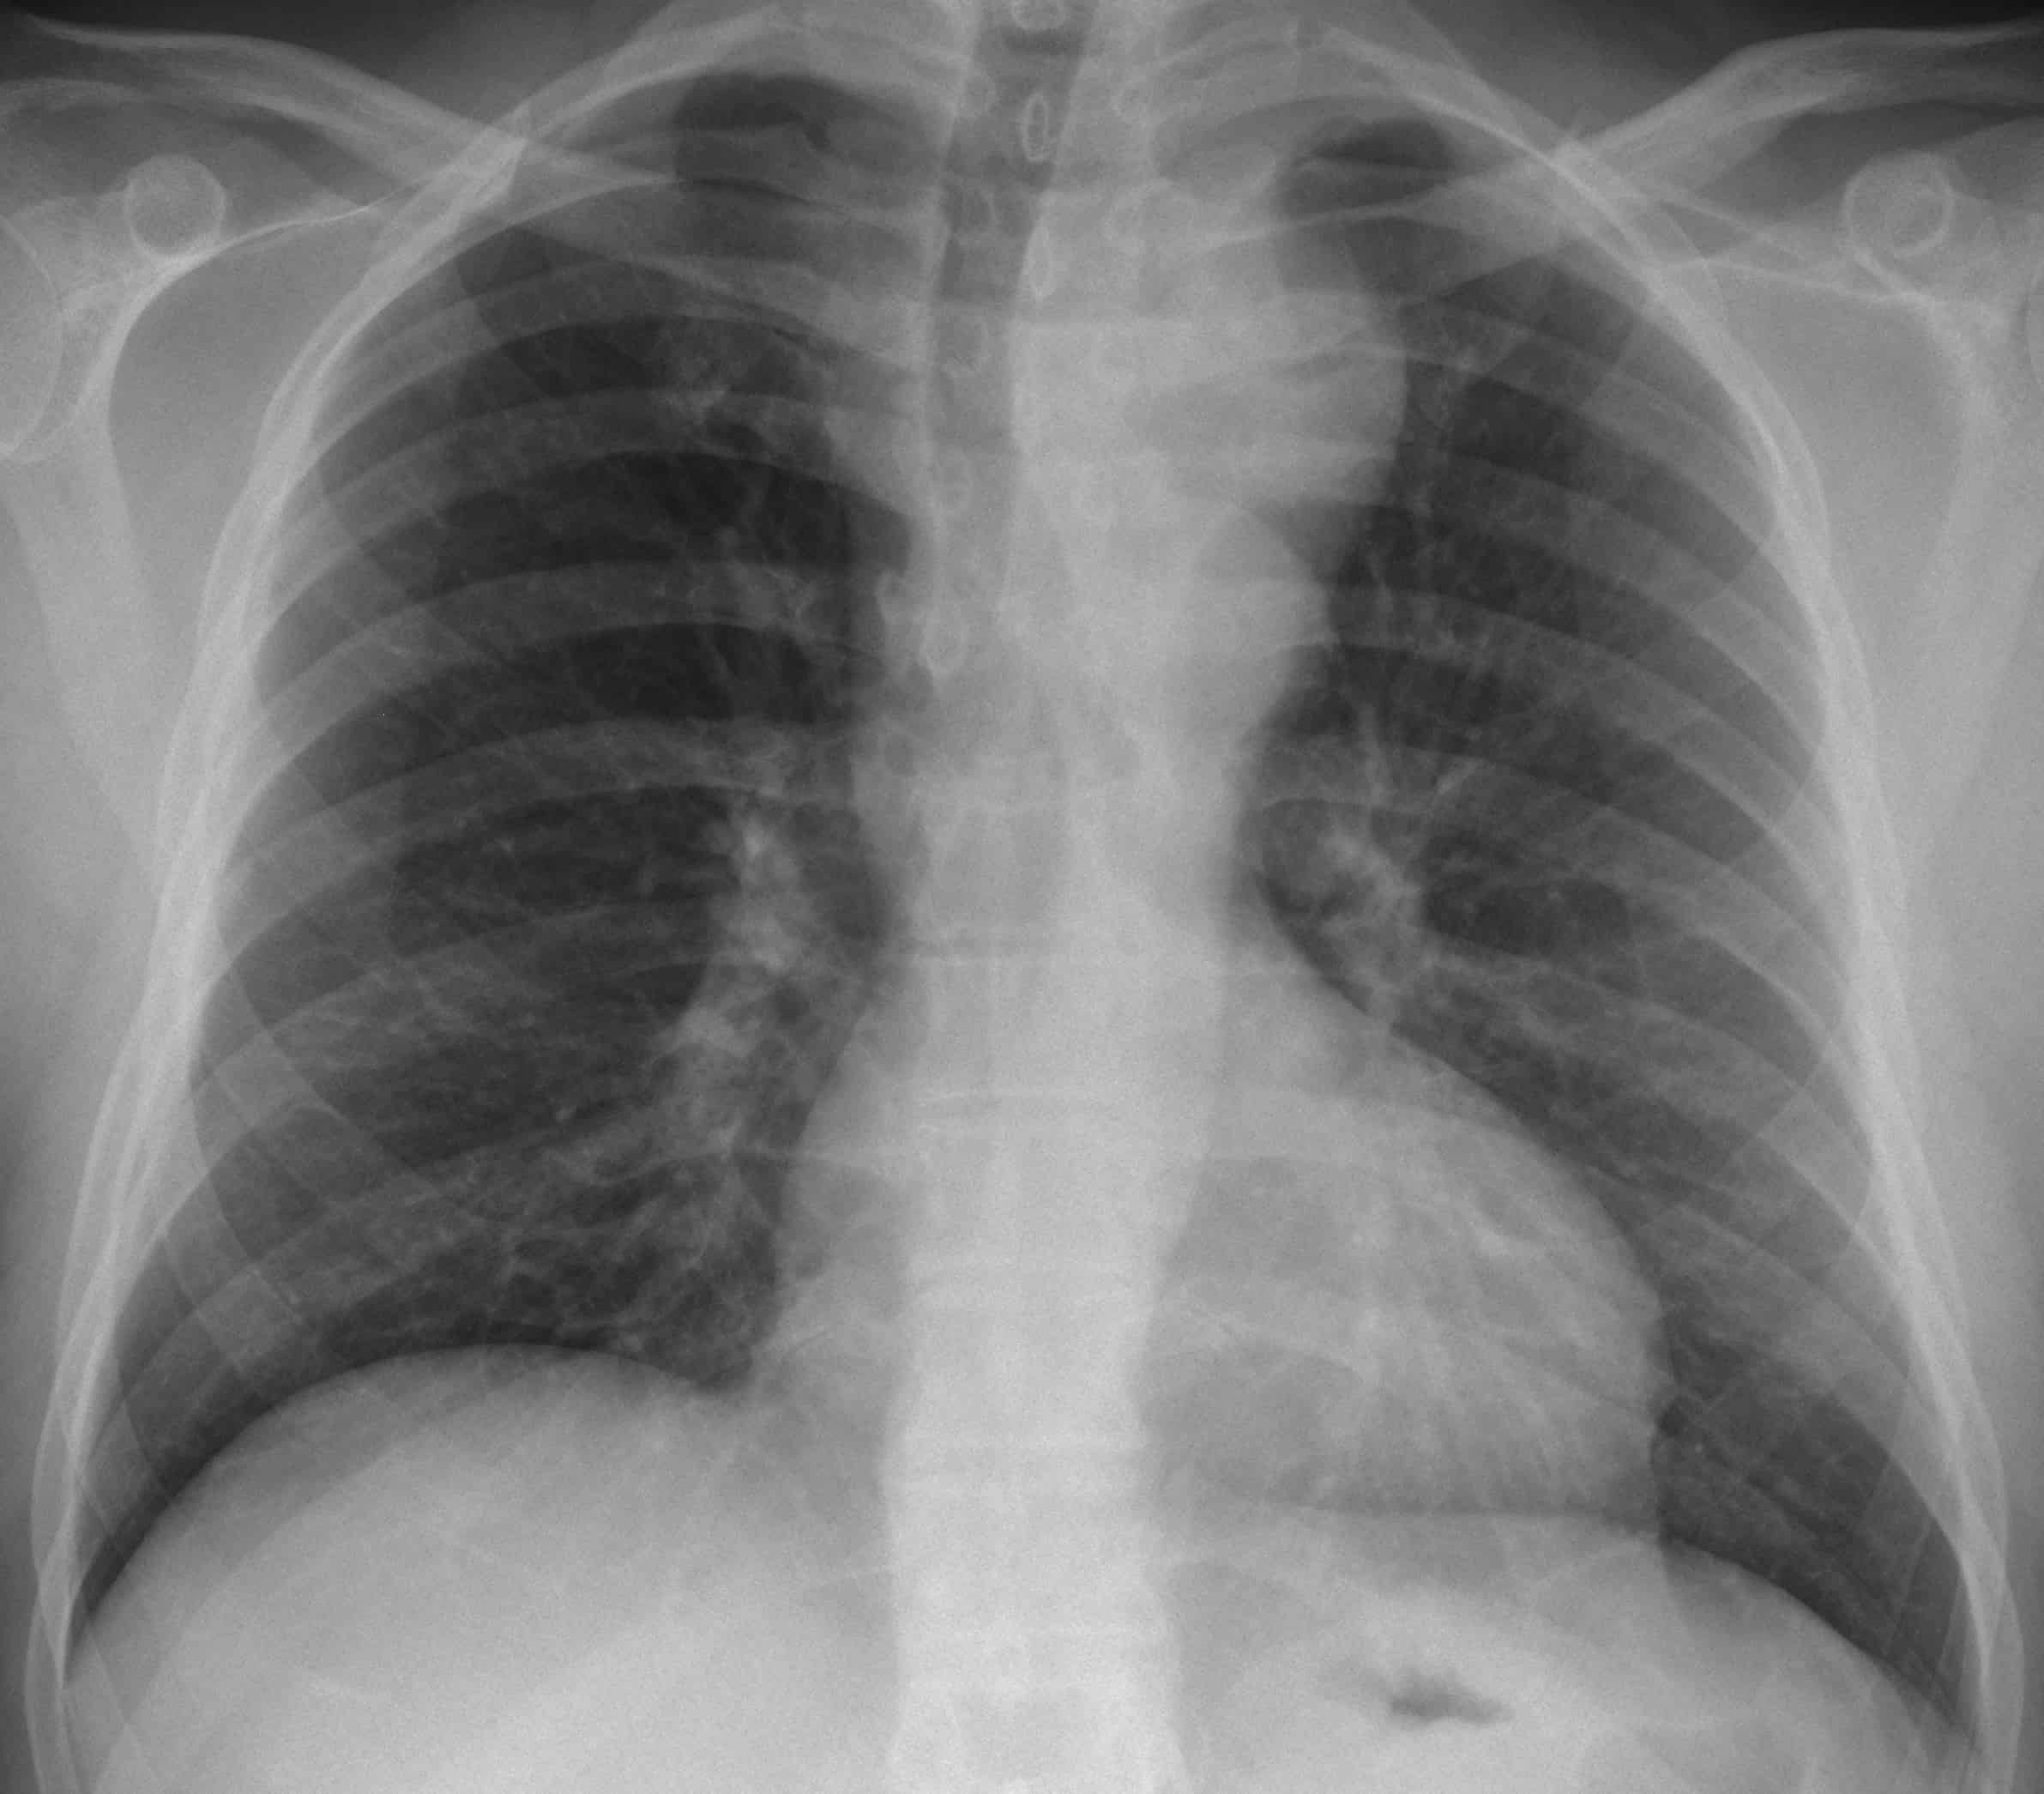

Phình ĐM chủ

» Thông tin: Nam giới – 45 tuổi.

» Lâm sàng: Đau ngực.